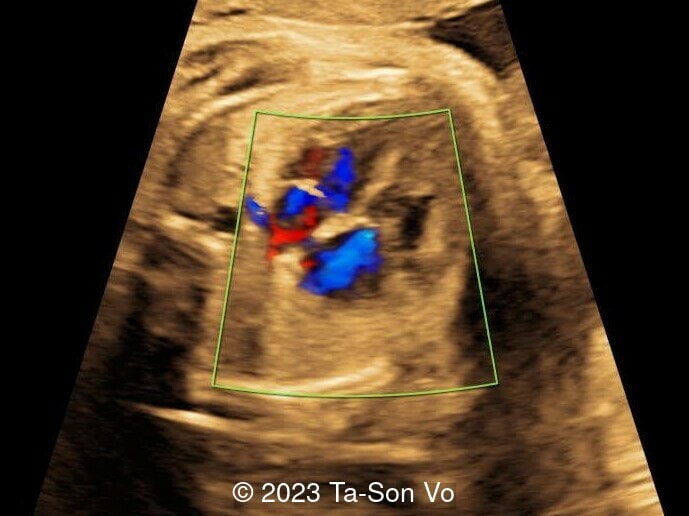

Level 2 ultrasound at 23 weeks and 28 weeks of gestation revealed thick nuchal and prenasal skin (Image 1), frontal bossing (Image 1,2), facial dysmorphism with a short nose, anteverted nostrils, flat nasal bridge, and long philtrum (Image 3,4), hypertelorism (Image 5), mega cisterna magna (Image 6) and polyhydramnios (Image 7). There was neither congenital diaphragmatic hernia nor cardiac defects with only mild tricuspid regurgitation (Image 8). Fetal biometry demonstrates a large head with rhizomelic limb shortening (Image 9).